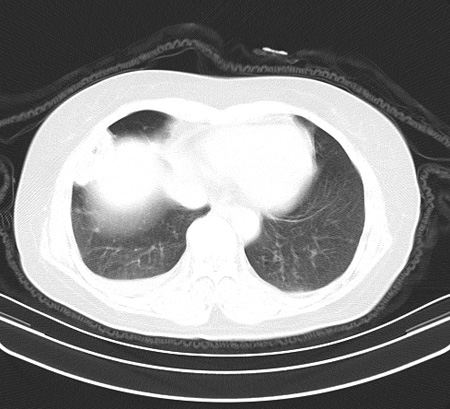

以下是引用余辉在2009-2-19 20:10:00的发言:[br]多考虑急性感染性病变,右中叶尚可见多枚小斑片状影,多为化脓性肺炎,双侧胸腔积液

以下是引用随光逐影在2009-2-19 20:33:00的发言:[br]1)考虑右肺炎症;建议抗炎治疗后复查。2)双侧胸腔积液(以右侧为甚)。

以下是引用花凤凰在2009-2-19 20:46:00的发言:[br]病人有发热,胸痛急性起病,主要病变位于右肺中叶外侧段,呈楔行改变,位于外带胸膜下,考虑为肺梗塞可能!!!!!!!!!!!!!!!!!!!!!!!!!!!!!!!!!!!